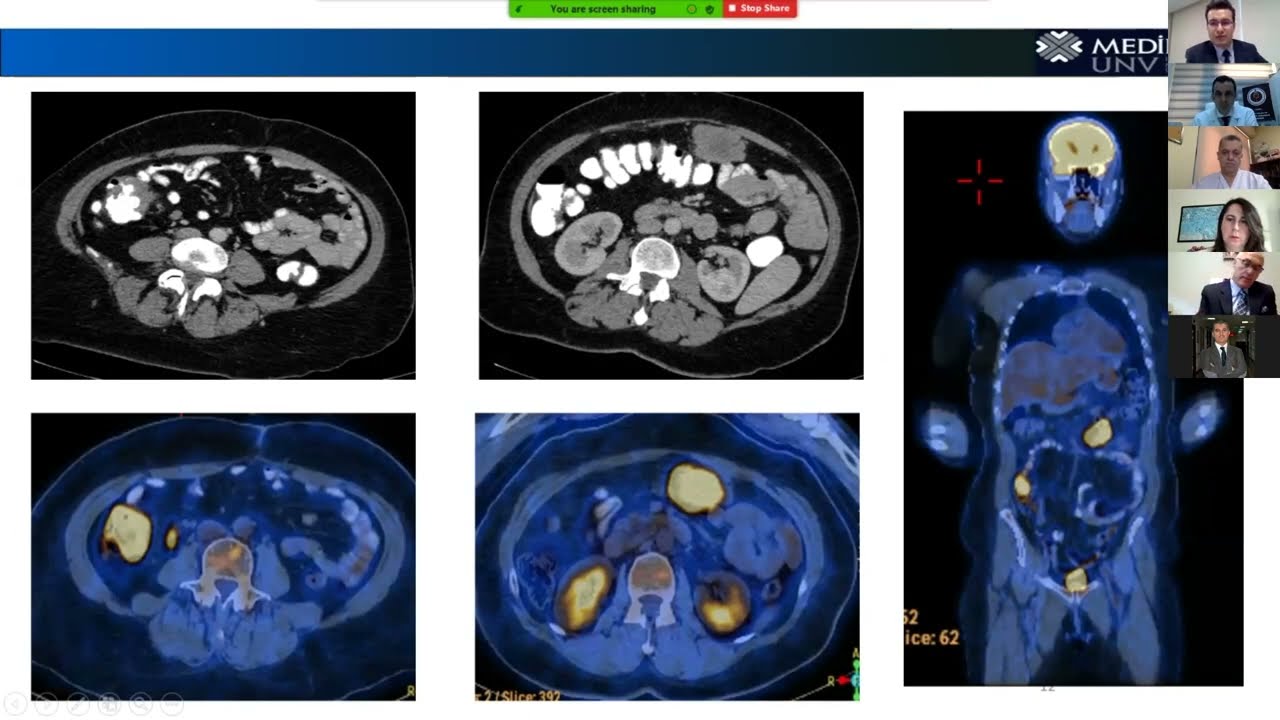

Cytoreductive surgery combined with heated intraperitoneal chemotherapy can provide oncological benefits in cancers that have spread to the peritoneum.

However, these are complex procedures with a high risk of complications. Being aware of these complications and learning preventive measures can improve patient outcomes.